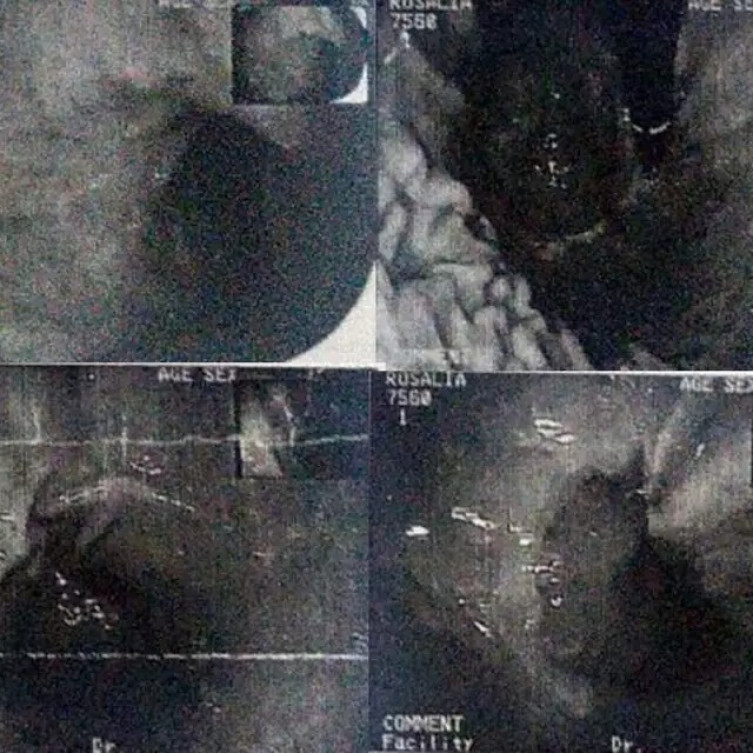

Exame de imagem feito na paciente para averiguar se ela sofreu alguma lesão por conta da gaze

A paciente que entrou com a ação foi submetida a uma cirurgia no hospital público em 2013. O erro foi identificado posteriormente, e a paciente teve que ser submetida a novas intervenções para a retirada do material, além de sofrer complicações por conta da infecção decorrente da negligência e poderia ter resultados ainda mais graves. A Justiça considerou que o incidente gerou não apenas sofrimento físico, mas também psicológico para a vítima.